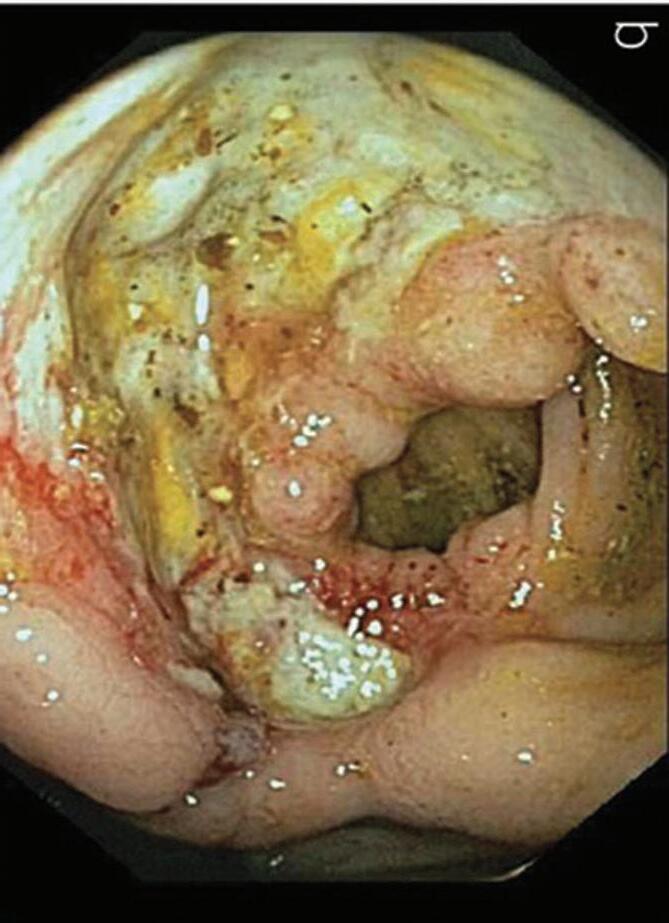

In a 1991 report in The American Journal of Gastroenterology, Drs. Alemayehu and Järnerot challenge prior orthodoxy that colonoscopy is contraindicated in patients with severe ulcerative colitis.